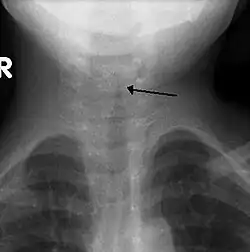

Croup (Laryngotracheobronchitis) is a viral infection of the vocal cords typically lasting five to six days. The main symptom is a barking cough and low-grade fever. On an X-ray, croup can be recognized by the "steeple sign", which is a narrowing of the trachea. It most commonly occurs in winter months in children between the ages of 3 months and 5 years. A severe form caused by bacteria is called bacterial tracheitis.[12]